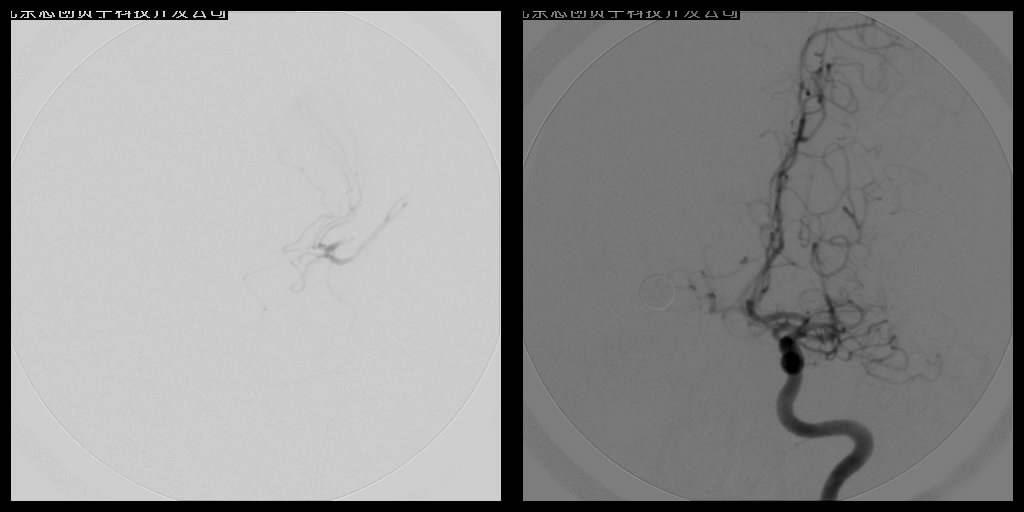

脑血管内介入栓塞术

血管栓塞术主要应用于出血性脑血管病的介入治疗,如对颅内动静脉畸形的栓塞、硬脑膜动静脉瘘栓塞、颈内动脉海绵窦瘘的栓塞、头颈部高血运肿瘤的栓塞等。